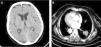

Presentamos el caso de una mujer no fumadora de 71 años de edad, con situs inversus totalis, que fue hospitalizada en el servicio de neurología por pérdida visual y auditiva progresiva de 2 meses de evolución. La exploración física mostró amaurosis e hipoacusia bilateral. La tomografía axial computarizada (TAC) cerebral no reveló lesiones intracraneales (fig. 1A) y la resonancia magnética (RM) con gadolinio no mostró potenciación leptomeníngea focal o difusa ni lesiones tumorales. Se efectuó una punción lumbar. El análisis anatomopatológico del líquido cefalorraquídeo (LCR) reveló la presencia de células adenocarcinomatosas, y las pruebas inmunohistoquímicas mostraron positividad al TTF-1 y a la citoqueratina 7, ambos indicativos de un origen pulmonar. La TAC torácica reveló una masa lobulada de 3cm en el lóbulo inferior derecho (LID) (fig. 1B). Se realizó una biopsia percutánea guiada mediante TAC, con la intención de obtener tejido tumor adicional para la secuenciación de la mutación EGFR. El análisis histológico mostró la ocupación del parénquima pulmonar por estructuras neoplásicas con características de adenocarcinoma y tinción difusa para TTF-1 y citoqueeratina 7. Durante el ingreso hospitalario, la paciente presentó una neumonía por aspiración y falleció. Una semana más tarde, la biopsia de la masa del LID indicó que el tumor albergaba una mutación EGFR G719C en el exón 18.